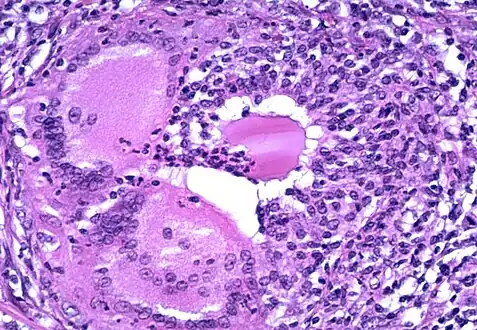

Above shows two parts of the thyroid that could potentially be affected if diagnosed with thyroiditis.